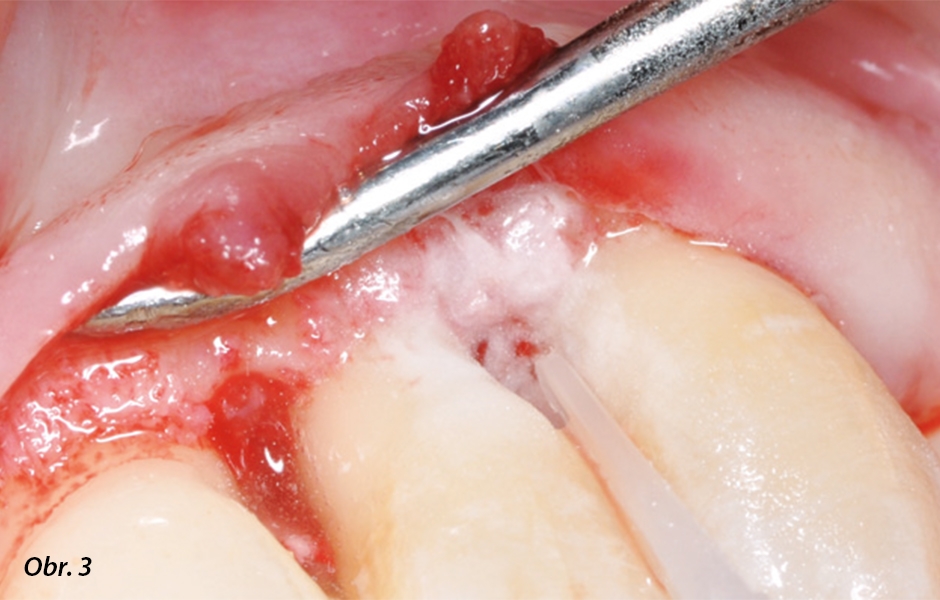

Mukoperiosteální lalok byl zvednut na úroveň alveolárního hřebene. Po vytvarování obrysu laloků jsme otevřeli okénka ke kořenům a defektům. Byly odstraněny granulační tkáně, defekty zcela vyčištěny a z povrchu kořene byl pomocí ultrazvukových nástrojů odstraněn zubní kámen.8 V dalším kroku jsme dekontaminovali povrchy kořene použitím profylaktického pískovače (Varios Combi Pro ve funkci perio) s práškem na bázi glycinu (Perio-Mate Powder).7, 10

Pružný hrot trysky umí sledovat obrysy zubu a lze jej přiložit na povrch kořene, aniž by došlo k případnému poškození parodontu. Tlak rozprašovaného prášku se uplatňuje supragingiválně, takže je jeho použití subgingiválně bezpečné. K irigaci prášku byl použit fyziologický roztok.11 Poté jsme již měli výhled na hladký, homogenní povrch kořene a defekty.

Ošetření povrchu kořene zubu 23 po debridementu

Čištění povrchu kořene pískovacím zařízením